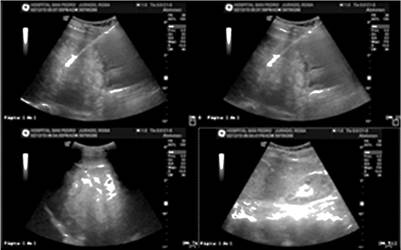

Se le realizan paraclínicos, con cuadro hemático dentro de parámetros normales, PCR elevada: 15 mg/dL, electrólitos, función renal, glucemia y tiempos de coagulación dentro de los valores normales. Ecografía de hígado y vías biliares que reportó múltiples lesiones focales de posible origen metastásico (Figura 1).

Cuando se sospecha metástasis de melanoma en el tracto digestivo se debe llevar a cabo el diagnóstico por imágenes apropiadas. La primera etapa básica de diagnóstico es la ecografía abdominal, este es un examen no invasivo y de bajo costo. Otro examen es la tomografía computarizada, cuya sensibilidad de identificación de metástasis de melanoma en el tracto digestivo es solo de 60%-70%. En cada caso, cuando las metástasis en el tracto digestivo se sospechan clínicamente, es necesario llevar a cabo otros exámenes a pesar de TAC negativo. El examen PET/TC garantiza mayor sensibilidad que la TAC en la identificación de metástasis de melanoma y debe llevarse a cabo si está disponible 4. En el reporte de caso, la ecografía y la TAC revelaron metástasis en el tracto digestivo (Figura 1 y 2).